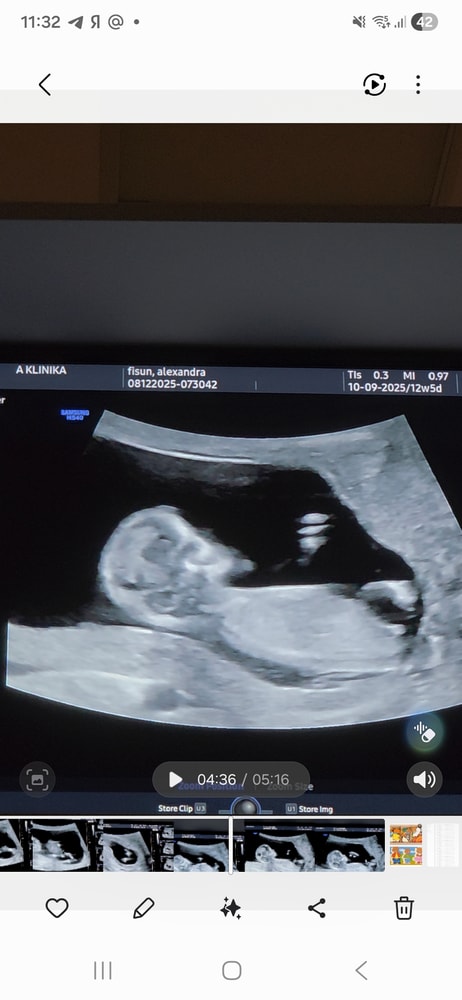

Мальчик или девочка УЗИ 12 недель

Половой бугорок смотрит вниз - девочка)

Александра Тарталетка, половой бугорок лежит горизонтально, девочка . Я тоже скриншоты делала , у меня мальчик) Изображение

Больше на мальчика конечно похоже ))))но точнее скажут позже )

Александра , сказали ножки скрещивает, не посмотреть) а это я скриншоты из видео сделала, потому что прям чтобы посмотреть не сбоку, а между ног действительно не получилось, только сбоку кадры)

Александра Тарталетка, по УЗИ можно предположить мальчика но это так же могут быть и половые губы как я читала они у девочек набухшие изначально поэтому по узи точно тут не скажешь )